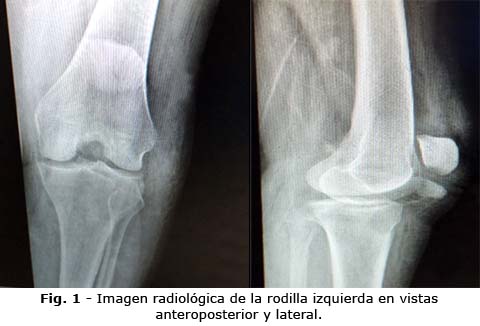

En las radiografías se evidenció solución de continuidad en la tuberosidad anterior de la tibia y ascenso de la rótula en la rodilla izquierda en las vistas antero posterior y lateral (Fig. 1).

Tras la obtención de los estudios complementarios se decidió realizar tratamiento quirúrgico por lesión del mecanismo extensor de la rodilla debido a avulsión de la tuberosidad tibial izquierda. La cirugía consistió en reducción abierta, osteosíntesis con un tornillo AO de tracción de 4,5 mm de diámetro por 32 mm de largo y cerclaje en 8 suprarrotuliano proximal y a 1 cm distal a la tuberosidad tibial (Fig. 2).